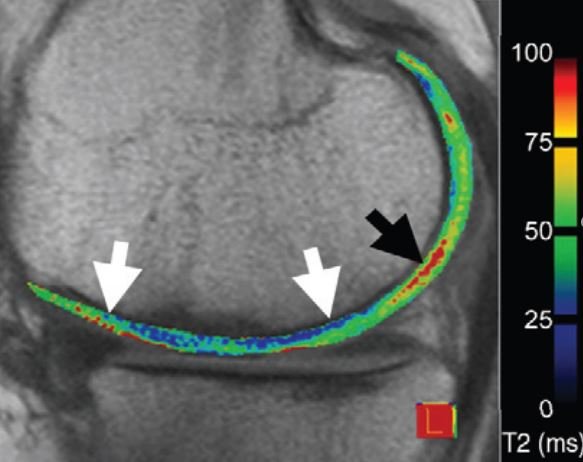

Cartilage assessment

Sagittal proton density weighted image shows the lateral tibio-femoral compartment 18 months after MACI of the lateral weight bearing femur. The repair zone is demarcated by long thin arrows and hypertrophy of the repair tissue is noted. At the posterior lateral tibia, there is a focal areaq of superficial cartilage thjinning and marked intrachondral hyperintensity of the native cartilage (large arrow). This finding of pathology distant to the repair zone is not covered by commonly applied cartilage repair grading schemes but might be relevant for long term outcome of the joint.